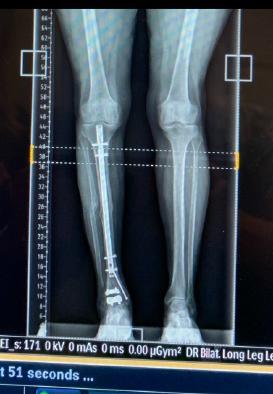

Before Surgery After Surgery